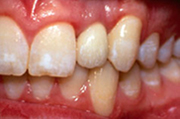

• Отлична естетика на съзъбието на пациента.

• Повишава се значително качеството на живот, самочувствието и увереността.